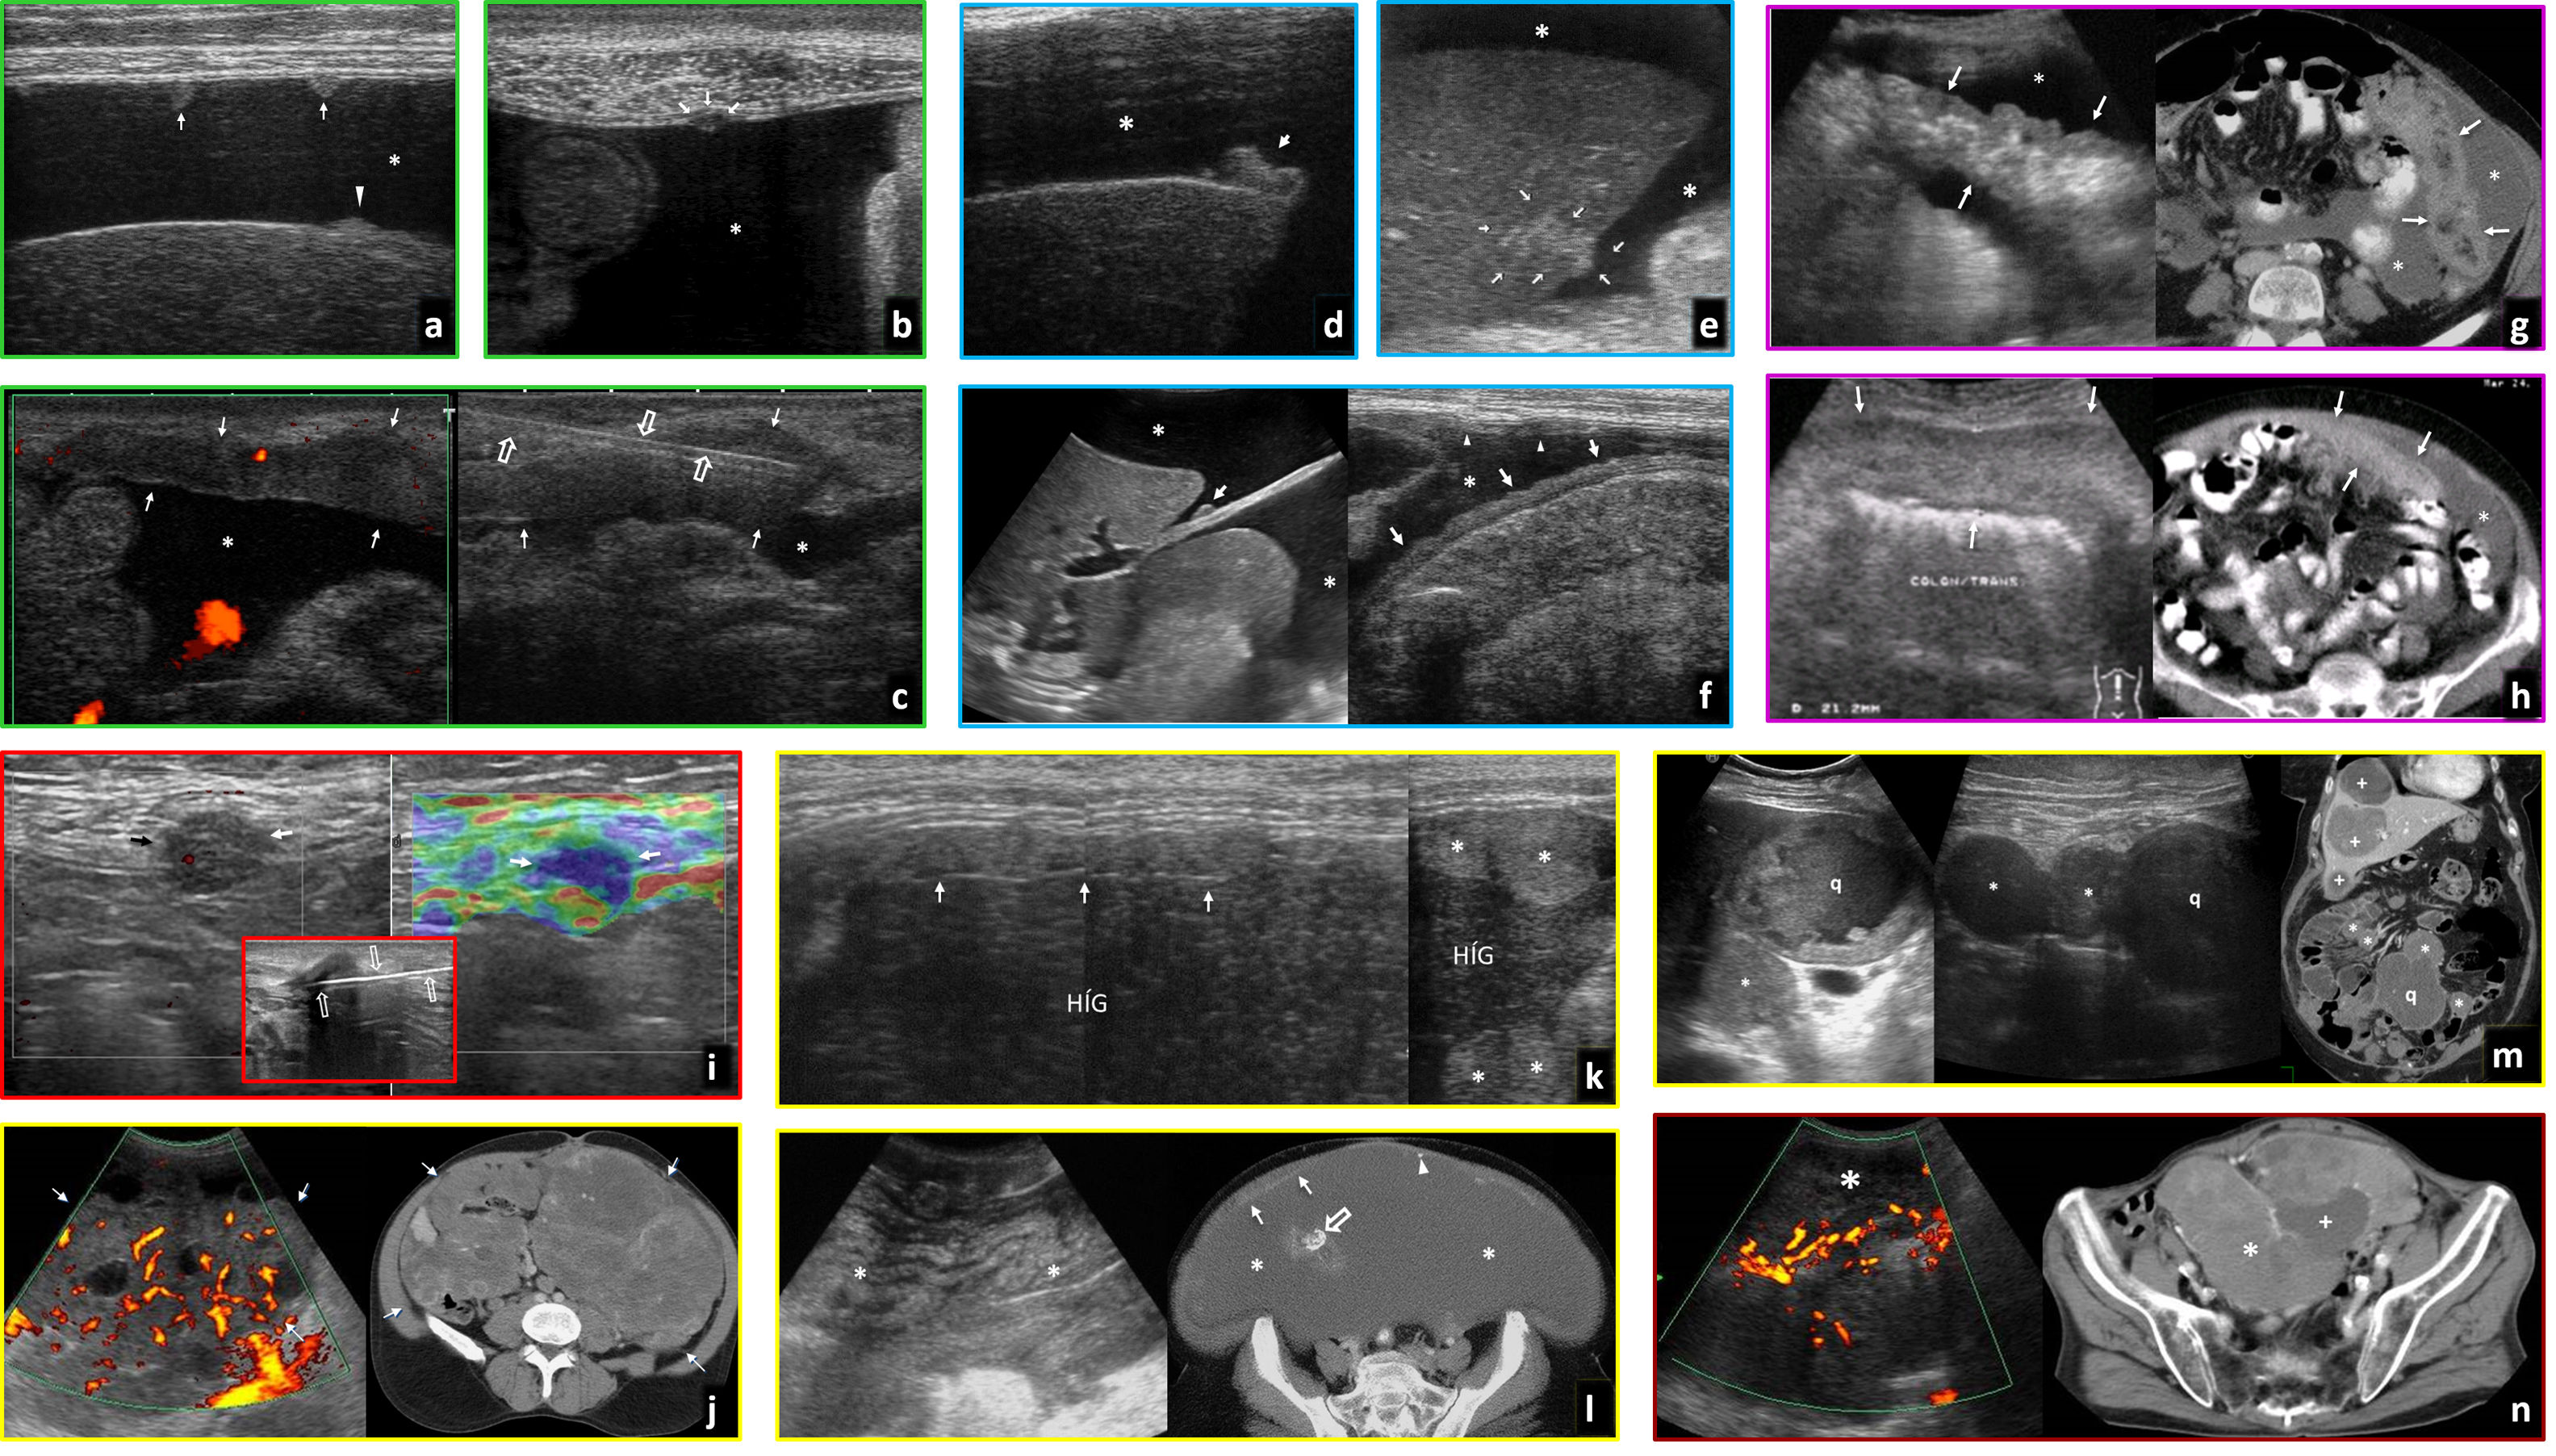

Lesiones polipoideas (fig. 5A-D)Hay evidencia de una secuencia pólipo-cáncer gastrointestinal, con modelos stepwise (sucesión de mutaciones o alteraciones epigenéticas), big bang (episodios masivos en fases iniciales) o de punctuated equilibrium (periodos de gran transformación alternando con fases de estatismo o cambios graduales)41. Se acepta una actitud conservadora para pólipos diminutos (<5 mm) y pequeños (6-9 mm), con riesgo de displasia o cáncer despreciable. Se detecta cáncer en el 1% de pólipos adenomatosos de 1-2cm y en el 50% de mayores de 3 cm. Los pólipos serrados planos, típicos del colon derecho, tienen un comportamiento menos agresivo del que se les atribuía clásicamente.

Pólipos y carcinomas. A) Pólipo adenomatoso hipoecogénico de 13 mm (flechas) en la luz del colon transverso, con un pedículo que sigue la estructura en capas de la pared (cabezas de flecha) y flujo demostrado en Doppler (derecha). Hallazgo incidental en varón de 77 años. B) Pólipo adenomatoso hipoecogénico (flechas) en el colon sigmoide, hallazgo incidental en varón de 44 años. La estabilidad de la imagen en el tiempo y la rigidez tisular, con tonos azules en la imagen de elastografía cualitativa de presión o strain (derecha), confirman el hallazgo. C) Carcinoma Hagitt 1 sobre pólipo adenomatoso hipoecogénico de 15 mm (flecha) en la luz del colon izquierdo distal, con un vaso en su interior en Doppler y una pequeña ulceración superficial (flecha hueca). Hallazgo incidental en ecografía por ateromatosis en varón de 67 años. En el recuadro, imagen de colonoscopia previa a resección. D) Carcinoma Hagitt 1 sobre pólipo adenomatoso hipoecogénico de 20 mm (flecha) en la luz del colon sigmoide, con un vaso en su pedículo en Doppler (cabeza de flecha). Hallazgo incidental en estudio por molestias abdominales inespecíficas en mujer de 78 años. En el recuadro, imagen durante la resección endoscópica. E) Adenocarcinoma infiltrante de colon sigmoide T2 N0 M0 en ecografía por anemia en varón pluripatológico de 85 años. Engrosamiento hipoecogénico infiltrante con retracción de la pared posterior del colon (flechas), sin rebasar la capa muscular propia hipoecogénica (cabezas de flecha). La ecografía es más precisa que la tomografía computarizada (TC) (no mostrada) en la estadificación locorregional en este caso, permitiendo un abordaje quirúrgico laparoscópico rápido y limitado en un paciente clínicamente complejo. F) Carcinoma polipoideo en recto inferior, hallazgo ecográfico empleando la vejiga (v) como ventana acústica. Lesión nodular hipoecogénica (flechas) de 33 mm. En el recuadro, curva intensidad/tiempo de ecografía con contraste para confirmar el hallazgo (vídeo 1). p: próstata. Imagen inferior: correlación en resonancia magnética (RM) sagital potenciada en T2 con gel endorrectal para estadificación locorregional. G) Carcinoma de transición colorrectal como masa exofítica ulcerada y necrótica que simula GIST. imagen superior: ecografía, sección transversal (izquierda) y longitudinal (derecha) sobre hipogastrio. Masa hipoecogénica heterogénea (flechas) por necrosis, con focos de gas (flechas huecas) por ulceración. Imagen inferior: TC sagital. La masa contacta con la cara anterior del recto-sigma (r). Se sospechó GIST, pero correspondió a un adenocarcinoma con un patrón infrecuente de presentación. H) Adenocarcinoma gástrico T4a N2 M0. Imagen superior: ecografía por síndrome constitucional en varón de 83 años. Engrosamiento hipoecogénico marcado e irregular de la pared del estómago (e: luz gástrica), con ulceraciones (no mostrado) y clara extensión nodular a la grasa del ligamento gastrocólico (cabezas de flecha). La elastografía (recuadro inferior izquierdo) muestra marcada rigidez tisular. Se ven también adenopatías regionales (flecha hueca en recuadro inferior derecho). Imagen inferior: TC coronal en fase portal. La gran delgadez del paciente hace que la estadificación sea menos precisa que con ecografía. I) Adenocarcinoma rectal T1 sobre pólipo velloso (flechas) en varón de 67 años. La ecografía endorrectal (izquierda) muestra una lesión polipoidea de ecogenicidad intermedia, definiendo con más precisión que la RM (derecha: T2 transversal con gel endorrectal) la indemnidad de la capa muscular propia (hipoecogénica), permitiendo la resección transanal. J) Adenocarcinoma de recto inferior T3a superficial en varón de 72 años. La ecografía endorrectal (izquierda) muestra con precisión un engrosamiento hipoecogénico excéntrico en la cara anterior del recto inferior, que transgrede la capa muscular propia hipoecogénica con nodulaciones superficiales (flechas), confirmando extensión T3 superficial. Se demuestra la preservación de un plano graso (cabezas de flecha) con la próstata (p). La RM transversal T2 (derecha) plantea dudas en este caso desde T2 hasta T4b por infiltración prostática. K) Mucocele apendicular. Imagen superior: hallazgo ecográfico incidental en mujer de 77 años con colecistitis aguda litiásica. Masa ovoidea con estructura interna en capas con ecogenicidades alternantes (patrón “en capas de cebolla” característico) en fosa iliaca derecha (flechas). Imagen inferior: la TC axial muestra finas calcificaciones parietales, pero no es capaz de demostrar la estructura mucinosa de la lesión quística con la precisión de la ecografía. L) Mucocele apendicular sobreinfectado y comunicado con el ciego. Imagen superior: ecografía en varón de 62 años con dolor abdominal y fiebre. Masa quística heterogénea en fosa iliaca derecha (flecha), con focos ecogénicos que representan gas (cabeza de flecha) y calcificaciones parietales (flecha hueca). Imagen inferior: la TC demuestra además la comunicación del mucocele con la luz del ciego (flecha discontinua).

La ecografía permite encontrar pólipos colónicos grandes (>1 cm), evitando o facilitando la detección precoz de cánceres, con especificidad del 94,4%, sensibilidad del 28,6% sin preparación42 y del 91% con hidrocolonosonografía43 en adultos. En niños con síntomas alcanza una sensibilidad del 47% y una especificidad del 100% sin preparación44 y del 95% y 100%, respectivamente, con enema de glicerina45. Son más accesibles en colon izquierdo y sigmoide y menos en recto y ángulo esplénico. También son detectables fuera del colon46,47. Aparecen como lesiones nodulares hipoecogénicas endoluminales persistentes, ocasionalmente con un pedículo que muestra continuidad con las capas de la pared. La detección de pequeños focos quísticos, de vascularización con Doppler o contraste y la elastografía, junto a un estudio cuidadoso, permite diferenciarlos de heces, haustras o Taeniae coli. Se correlacionan con malignidad el tamaño, la infiltración en profundidad en la pared y la ulceración48. Se ha descrito la utilidad de la ecografía laparoscópica con enema de suero en su detección intraoperatoria, con algunas ventajas sobre el tatuaje con tinta china49,50.

Carcinoma (fig. 5E-l, vídeo 1)Cuando no es polipoideo se comporta habitualmente como un engrosamiento parietal hipoecogénico excéntrico o concéntrico asimétrico de un tramo gastrointestinal corto, con límites abruptos y pérdida de la estratificación29,35,36. Raramente aparece como una masa exofítica, simulando un tumor del estroma gastrointestinal (GIST). Es habitual que haya ulceraciones (focos de gas intratumorales), rigidez, estenosis (luz fija y peristaltismo proximal ineficaz) y una afectación ganglionar regional moderada. La experiencia y una exploración cuidadosa (que debe intensificarse si hay alta sospecha o metástasis hepáticas) facilitan la detección en regiones difíciles.

Algunos artículos muestran valores diagnósticos por encima del 80% para carcinomas gástricos y colónicos tomando como referencia la endoscopia51,52, mejores si se excluye el recto. Un estudio mostró en cáncer de colon coincidencia moderada (64%) con el estadio T histológico, que se elevaba al 89% (buena) estableciendo grupos con interés de planificación quirúrgica y pronóstico52. La hidrocolonosonografía alcanza mejores resultados que la TC53, pero ha ido perdiendo interés por mala tolerancia. Autores chinos consiguen buenos resultados en la detección y caracterización de carcinoma y otras lesiones gástricas46,47 empleando una técnica de doble contraste (intravenoso y oral derivado de arroz y soja, de consistencia y ecogenicidad intermedias, con buena transmisión, no disponible en nuestro entorno).

La ETR puede superar a la RM en la definición T1-T2 (seleccionando candidatos a resección endoscópica o transanal), T2-T3 superficial y T3 superficial-profunda (seleccionando candidatos a neoadyuvancia)34. Exige experiencia y es menos útil en T4 y N.

El mucocele apendicular es la acumulación de moco, con ecogenicidades diversas, a veces alternantes (“en capas de cebolla”), en la luz de un apéndice distendido (>15 mm), ocasionalmente con gas (por sobreinfección y/o comunicación con la luz cecal) o calcificación parietal. Una pared irregular o nódulos sólidos deben hacer sospechar un cistoadenocarcinoma subyacente. Su perforación puede llevar a un pseudomixoma peritoneal35,54.

Tumores neuroendocrinos (TNE) (fig. 6, vídeo 2)Los gastrointestinales asientan generalmente en la capa submucosa. La OMS los considera potencialmente malignos, estableciendo tres grados de agresividad según la proliferación celular. Dentro del grupo G3, los tumores con Ki-67 >50 son carcinomas. Pueden aparecer en síndromes genéticos (MEN-1, von-Hippel-Lindau, esclerosis tuberosa y neurofibromatosis-1). Muchos segregan hormonas o aminas que condicionan el cuadro clínico y facilitan la detección analítica (serotonina o derivados, cromogranina-A, gastrina, sinaptofisina, enolasa específica neuronal, etc.) o con procedimientos de medicina nuclear (destacando la PET-TC con 68Ga-DOTATATE por la expresión del receptor SSTR2 en tumores diferenciados, quedando la PET-TC con 18FDG para valorar la actividad metabólica en desdiferenciados)55–57.

Tumores neuroendocrinos. A) Tumor carcinoide de íleon terminal. Mujer de 62 años con vómitos y dolor abdominal. Antecedente de macroadenoma hipofisario intervenido. Imagen superior: ecografía. Imagen inferior: tomografía computarizada (TC) coronal. Lesión nodular hipoecogénica con abundante vascularización en Doppler y TC (flechas), en el ángulo interno de tramo plegado de íleon distal (+), con peristaltismo ineficaz a tiempo real (vídeo 2). Además, adenopatías hipoecogénicas y vascularizadas (cabezas de flecha) en meso regional tumefacto y ecogénico (m). Se diagnostica MEN-1. En el recuadro: implante endometriósico (*) en íleon terminal (+) en otra paciente, como nódulo hipoecogénico que infiltra la serosa, retrayendo el asa y respetando las capas profundas, que muestra hallazgos similares y con el que hay que establecer diagnóstico diferencial (no vascularizado y sin afectación adenopática en este caso). B) Carcinoide ileal solo manifestado como masa mesentérica. Imagen superior: biopsia percutánea (flechas huecas) guiada ecográficamente de nódulo mesentérico hipoecogénico (flecha), que demostró metástasis ganglionar de tumor neuroendocrino. Imagen inferior: TC coronal con contraste oral e intravenoso. Nódulos adenopáticos mesentéricos (flechas). En la cirugía se identificó un carcinoide milimétrico intestinal primario y retrospectivamente podría corresponder al pequeño defecto de repleción indicado por la cabeza de flecha. C) Carcinoides yeyunales múltiples y metástasis ganglionares mesentéricas. Mujer de 71 años con molestias abdominales inespecíficas. Imágenes superiores: ecografías. Centrales e inferiores: imágenes axiales de entero-TC en dos planos diferentes. Se detectan hasta 5 tumores hipoecogénicos e hipervasculares (uno no mostrado) en tramos plegados de yeyuno (flechas), con un pequeño conglomerado adenopático también hipervascular e hipoecogénico en el meso tributario (cabezas de flecha). D) Síndrome de Zollinger-Ellison por tumor neuroendocrino de tipo II (gastrinoma) de tracto digestivo superior. Varón de 44 años con vómitos, diarrea y shock. Imagen izquierda: ecografía. Imagen derecha superior: TC axial. Abundante líquido en estómago (e), duodeno (d) y yeyuno proximal (no mostrado), con marcado engrosamiento de pliegues gástricos (cabezas de flecha). Medial al duodeno y posterior al páncreas se ve un nódulo hipervascular y levemente ecogénico (flechas) en el seno de una estructura ganglionar. Esta región está dentro del llamado “triángulo del gastrinoma”. Derecha centro: gammagrafía con octeótrida. Se confirma captación por parte del nódulo (flecha). También hay hipergastrininemia. Derecha inferior: pieza quirúrgica del gastrinoma (flechas) en el seno de un ganglio. E) Carcinoma neuroendocrino gástrico de tipo III. Varón de 59 años con síndrome constitucional. La ecografía muestra abundantes metástasis hepáticas (m) y, empleando el bazo (b) como ventana acústica, un tumor infiltrante en la curvatura mayor del estómago. Se sospechó un adenocarcinoma, pero la biopsia endoscópica demostró un carcinoma neuroendocrino. F) Tumor neuroendocrino rectal. Hallazgo en la colonoscopia por test de sangre oculta en heces positivo en varón de 62 años. Imagen superior: ecografía transrectal. Imagen inferior: RM T2 axial. Tumor de 7× 5 mm (flechas) con comportamiento hipoecogénico e hipointenso en T2, situado en la parte profunda de la capa submucosa del recto inferior, con moderada rigidez tisular en elastografía (recuadro central), con strain ratio de 10 con respecto a la pared rectal normal. Se realizó una resección endoscópica transanal.

Los más frecuentes son los carcinoides de íleon distal, donde suponen la neoplasia más habitual. Es un tumor submucoso pequeño (15-35 mm), hipoecogénico o con halo ecogénico35,37,56. La secreción de serotonina hace que pueda provocar obstrucción por retracción intestinal. La endometriosis puede simularlo35. Tiende a extenderse al mesenterio como adenopatías discretas o en forma de masas desmoplásicas hipoecogénicas, con frecuentes calcificaciones, que pueden ser el hallazgo dominante y provocar congestión mesentérica y del intestino tributario35,36,55,56. La ecografía detecta el 13-76,5% de los tumores primarios (26-40% múltiples)55,56. Tanto estos como las metástasis ganglionares o hepáticas realzan intensa y precozmente, a veces periféricamente35,58. La intensidad y el patrón de realce y lavado se han correlacionado con el grado tumoral58.

En duodeno y yeyuno proximal son muy infrecuentes. Pueden darse carcinoides o gastrinomas55,59, en cualquier caso, con adenopatías habituales y comportamiento menos desmoplásico. Los TNE suponen un 1% de las neoplasias gástricas. Los de tipo I (70-80%) son secundarios a gastritis crónica atrófica, no invasivos y pequeños. Los de tipo II (5-6%) son gastrinomas, también no invasivos y pequeños, y pueden producir síndrome de Zollinger-Ellison. Los de tipo III (15-20%) son invasivos y agresivos, simulando adenocarcinoma55,56.

El recto es la segunda localización de TNE gastrointestinales. Son pequeños y localizados, con buen pronóstico56. En ETR aparecen como hipoecogénicos, circunscritos a la submucosa.

Los TNE colónicos son muy raros y agresivos, si excluimos los apendiculares (donde representan el 60% de tumores), hallazgo incidental en pieza de apendicectomía en un 70% de los casos56, en general con buen pronóstico.